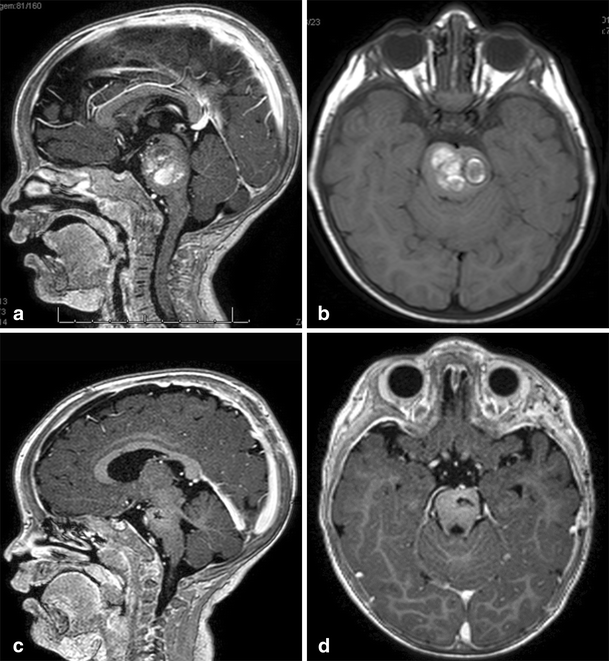

Fig. 14

figure 14

a, b 8-month-old patient with a large lesion in the anterior and superior portion of the pons, approached via orbito-fronto zygomatic via the supratrigeminal entry zone. c, d 6-month postoperative follow-up after complete resection of the lesion

Fig. 15

figure 15

a, b 10-year-old patient with tetraparesis. Tumor operated with a pre-sigmoid approach. c, d Postoperative control 10-year after gross total resection, showing no evidence of tumor